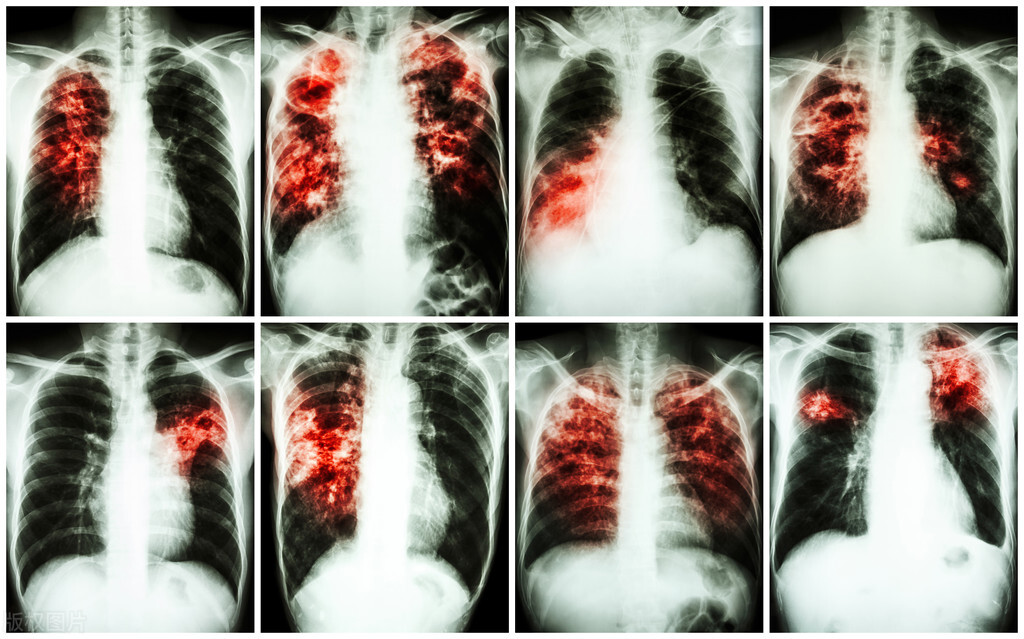

特发性肺纤维化(又称IPF)是一种原因不明的肺间质炎症性疾病,主要病理特点为肺间质和肺泡腔内纤维化和炎细胞浸润混合存在。正常的呼吸功能出现困难,主要表现为干咳、进行性呼吸困难,肺部听诊时可听到湿啰音或捻发音,如果做x线检查,会发现肺部早期呈毛玻璃状,典型改变弥漫性线条状、结节状、云絮样、网状阴影、肺容积缩小,而肺功能检查可见肺容量减少、弥散功能降低和低氧血症。

2形态上,肺纤维化中晚期出现双肺体积缩小,肺总量、肺活量、残气量及潮气量均明显减少,与“肺痿”原义相吻合。

4从临床特点而言,肺间质纤维化病程日久,迁延不愈,“初病气结在经,久则血伤入络”,晚期呈蜂窝肺(网格状改变),甚至毁损肺,肺功能丧失殆尽。这正与肺痿沉痾之肺叶萎弱不用,迁延反复,久治不愈之特点相对应。